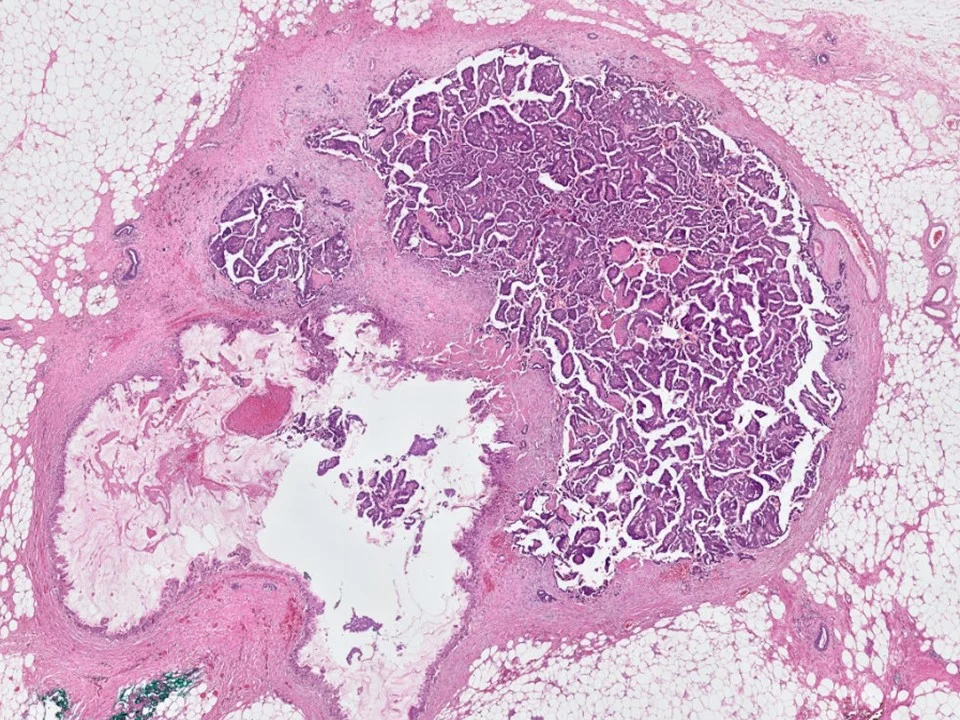

Encapsulated Papillary Carcinoma